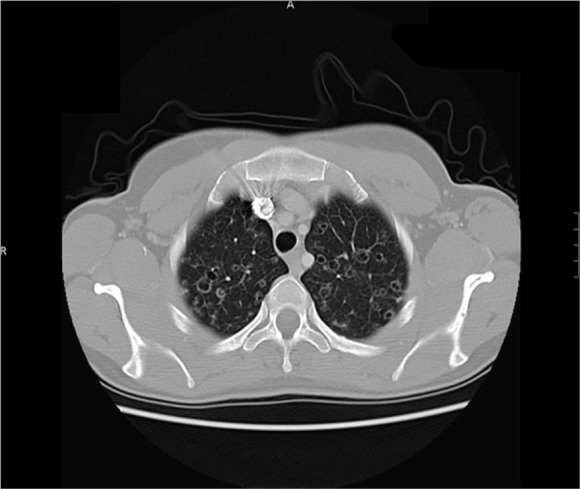

肺朗格汉斯细胞组织细胞增多症(PLCH)是一种罕见的弥漫性肺实质疾病,占所有间质性肺疾病的3%。PLCH既可作为多系统朗格汉斯细胞组织细胞增多症(LCH)的一部分发生,也可作为孤立的肺部疾病发生。在大约50-70%的LCH病例中观察到孤立的肺部受累,发病年龄在20 - 40岁之间无性别差异。吸烟是唯一确定的环境风险因素。PLCH的特点是朗格汉斯细胞浸润,通常以细支气管为中心分布。肺部病变可能发生在慢性全身性疾病之后,也可能是疾病的最初征兆。本研究的目的是(1)报告5例罕见的成人PLCH病例;(2)探讨PLCH与间质性肺纤维化的关系;(3)对PLCH的流行病学、病理生理学、诊断、治疗和预后进行简明的综述,以提高肺科医生和内科医生对PLCH的认识。

Pulmonary Langerhans cell histiocytosis (PLCH) is a rare diffuse parenchymal lung disease representing 3% of all interstitial lung diseases. PLCH occurs either as part of multi-system Langerhans cell histiocytosis (LCH) or an isolated disease of the lung. Isolated involvement of lungs is observed in approximately 50-70% of LCH cases and the age of onset peaks between 20 and 40 years without gender difference. Cigarette smoking is the only identified environmental risk factor. PLCH is characterized by Langerhans cell infiltrates that in general are in a bronchiolocentric distribution. Pulmonary lesions can occur after chronic systemic disease or are an initial sign of disease. The aims of this study are to (1) report five rare cases of PLCH in adults; (2) discuss the relationship of PLCH with interstitial lung fibrosis; (3) provide a concise review of PLCH epidemiology, pathophysiology, diagnosis, treatment, and prognosis to improve the knowledge of PLCH by pneumologists and internal medicine physicians.